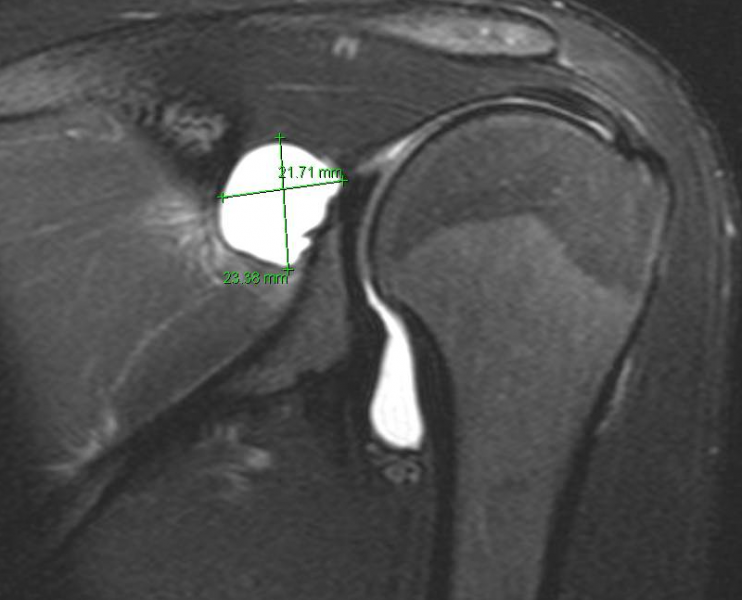

Spinoglenoid Cyst on MRI

Join fluid has formed a cyst that is putting pressure on the nerve branch to the infraspinatus.

These coronal views show the fluid leak from the labral tear and the cyst that is quite large.